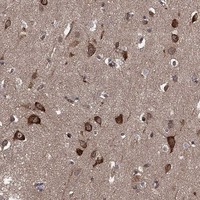

Immunohistochemical staining of human cerebral cortex shows strong cytoplasmic positivity in neuronal cells.